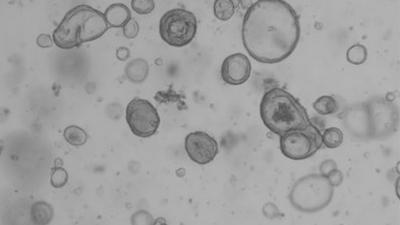

Het Catharina Ziekenhuis is een onderzoek gestart naar een nieuwe behandeling voor patiënten met uitgezaaide darmkanker in het buikvlies.